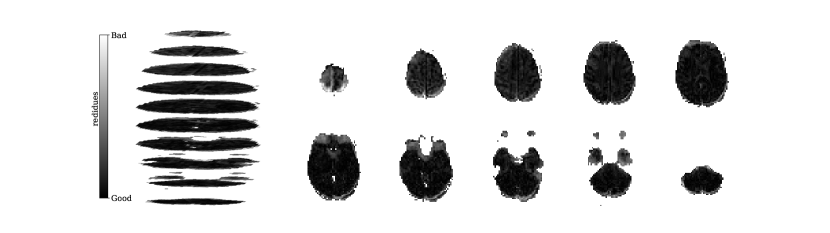

Figure 2 illustrates the distribution of residues (observed vs. estimated differences) on the fMRI volumes for the NODDI dataset. Clearly, by visual inspection, (iv) model has the darker and biggest area of shaded regions, which implies a better coverage across the brain regions and better synthesis quality. Models with topographical attention, (ii) and (iv), corresponding to Figures 2(b) and 2(d), respectively, significantly improve the synthesis, as shown by the darker and bigger areas against (i) and (iii) depicted in Figures 2(a) and 2(c), respectively. Particularly, we notice that models (i) and (iii) report difficulty in the retrieval of haemodynamical activity located in occipital and parietal lobes.

To better address which regions our baselines had more difficulty retrieving, the normalized residues were computed and are illustrated in Figure 3. Baselines – corresponding to models (i) and (ii), shown in Figures 3(a) and 3(b) respectively, which correspondingly implement a linear projection in the latent space and topographical attention –, have difficulty retrieving the prefrontal, occipital and parietal lobes, as the shade tends to a lighter grey in that region. Model (iv), shown in Figure 3(d), does not show a noticeable region with a lighter tone of grey, which implies no evident difficulty in retrieving haemodynamical activity across the different brain regions.